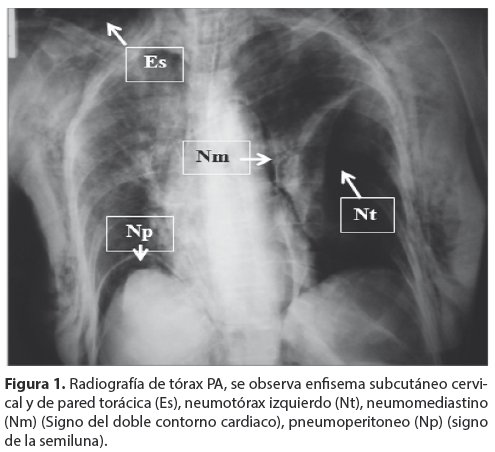

<body><![CDATA[<p align="justify">&nbsp;</p>     <p align="justify"><font size="3" face="Verdana"><b>Presentación del caso</b></font></p>     <p align="justify"><font face="Verdana" size="2">Paciente femenina de 80 años de edad, que llega a la sala de emergencias, y refiere dolor abdominal, de inicio súbito, sin causa aparente, a nivel de epigastrio, de intensidad moderada, difuso, tipo opresivo, sin irradiación. Antecedentes patológicos de Hipertensión Arterial Sistémica (HAS), tratada con inhibidores de la enzima convertidora de la angiotensina, síndrome depresivo, colecistectomizada hace 15 años.</font></p>     <p align="justify"><font face="Verdana" size="2">Al ingreso se encuentra en regular estado general, piel y mucosas ligeramente ictéricas. Signos vitales estables.</font></p>     <p align="justify"><font face="Verdana" size="2">El abdomen está blando depresible, con dolor a la palpación profunda en hipocondrio derecho y epigastrio, ruidos hidroaéreos presentes, sin evidencia de signos de irritación peritoneal. Los exámenes de laboratorio reportaron una leucopenia de 4 000 &#956;L, bilirrubina total de 2,9 mg/dl, bilirrubina directa de 2,1 mg/dl bilirrubina indirecta de 0,8mg/dl. La radiografía de tórax al ingreso no tenía evidencia de patología relevante; la ecografía abdominal informa colédoco a 13 mm, (sin poder descartar coledocolitiasis).</font></p>     <p align="justify"><font face="Verdana" size="2">La paciente es hospitalizada para la realización de estudios complementarios, con los diagnósticos de síndrome ictérico obstructivo y síndrome de dilatación de VBP a descartar.</font></p>     <p align="justify"><font face="Verdana" size="2">Se realiza CPRE para exploración de vías biliares, durante la cual e logró canular la vía biliar con posterior evacuación de litos (coledocolitiasis), con drenaje de bilis clara. Posterior al procedimiento, al examen físico presenta enfisema subcutáneo cervical y de pared torácica, dificultad respiratoria importante, cianosis distal, con rápido deterioro del estado general. Se procedió a introducir una sonda nasogástrica, observándose débito gástrico bilioso e imagen sugerente de abundante aire. Se realiza una radiografía de tórax PA (<a href="#f1">Fig. 1</a>) que informa la existencia de enfisema subcutáneo que afecta al cuello y pared del tórax, neumotórax izquierdo, neumomediastino (signo del doble contorno cardiaco), pneumoperitoneo (Signo de la semiluna). </font></p>     <p align="justify"><a name="f1"></a></p>     <p align="center"><img src="/img/revistas/gmb/v37n1/a10_figura_01.jpg" width="495" height="452"></p>     <p align="justify"><font face="Verdana" size="2">En la radiografía de abdomen en decúbito supino (<a href="#f2">Fig. 2</a>) se observa ambos músculos psoas bien delimitados, al igual que los márgenes renales, indicando aire en el espacio retroperitoneal. </font></p>     ]]></body>